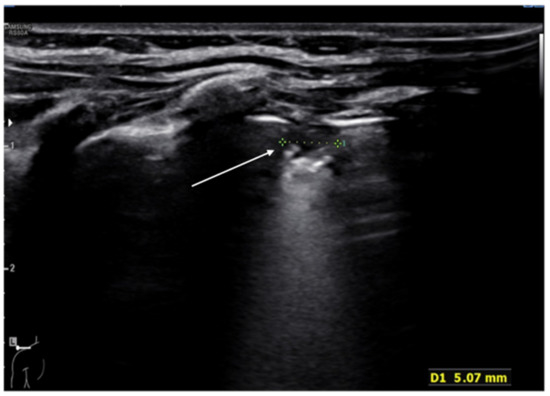

In bronchiolitis, the main ultrasound findings are: areas of subpleural consolidations defined as hypoechogenic areas with parenchymatous appearance and irregular margins, the presence of coalescent B-lines (three or more B-lines in each intercostal space) up to the “white lung” or focal presence of multiple B-lines (one or two B-lines in each intercostal space) and abnormalities of the pleural line (Figure 8 and Figure 9) [47]. Several studies demonstrated that lung ultrasound findings strictly correlate with the clinical evaluations in infants with bronchiolitis [48,49], and the 2020 consensus established LUS as a useful tool in assessing the severity of the disease [37]. Therefore, LUS could be used as support of the clinical examination in the identification of infants who may require more intensive care as supplementary oxygen or respiratory support [36].

Figure 9.

Bronchiolitis. Subpleural consolidation (white arrow).